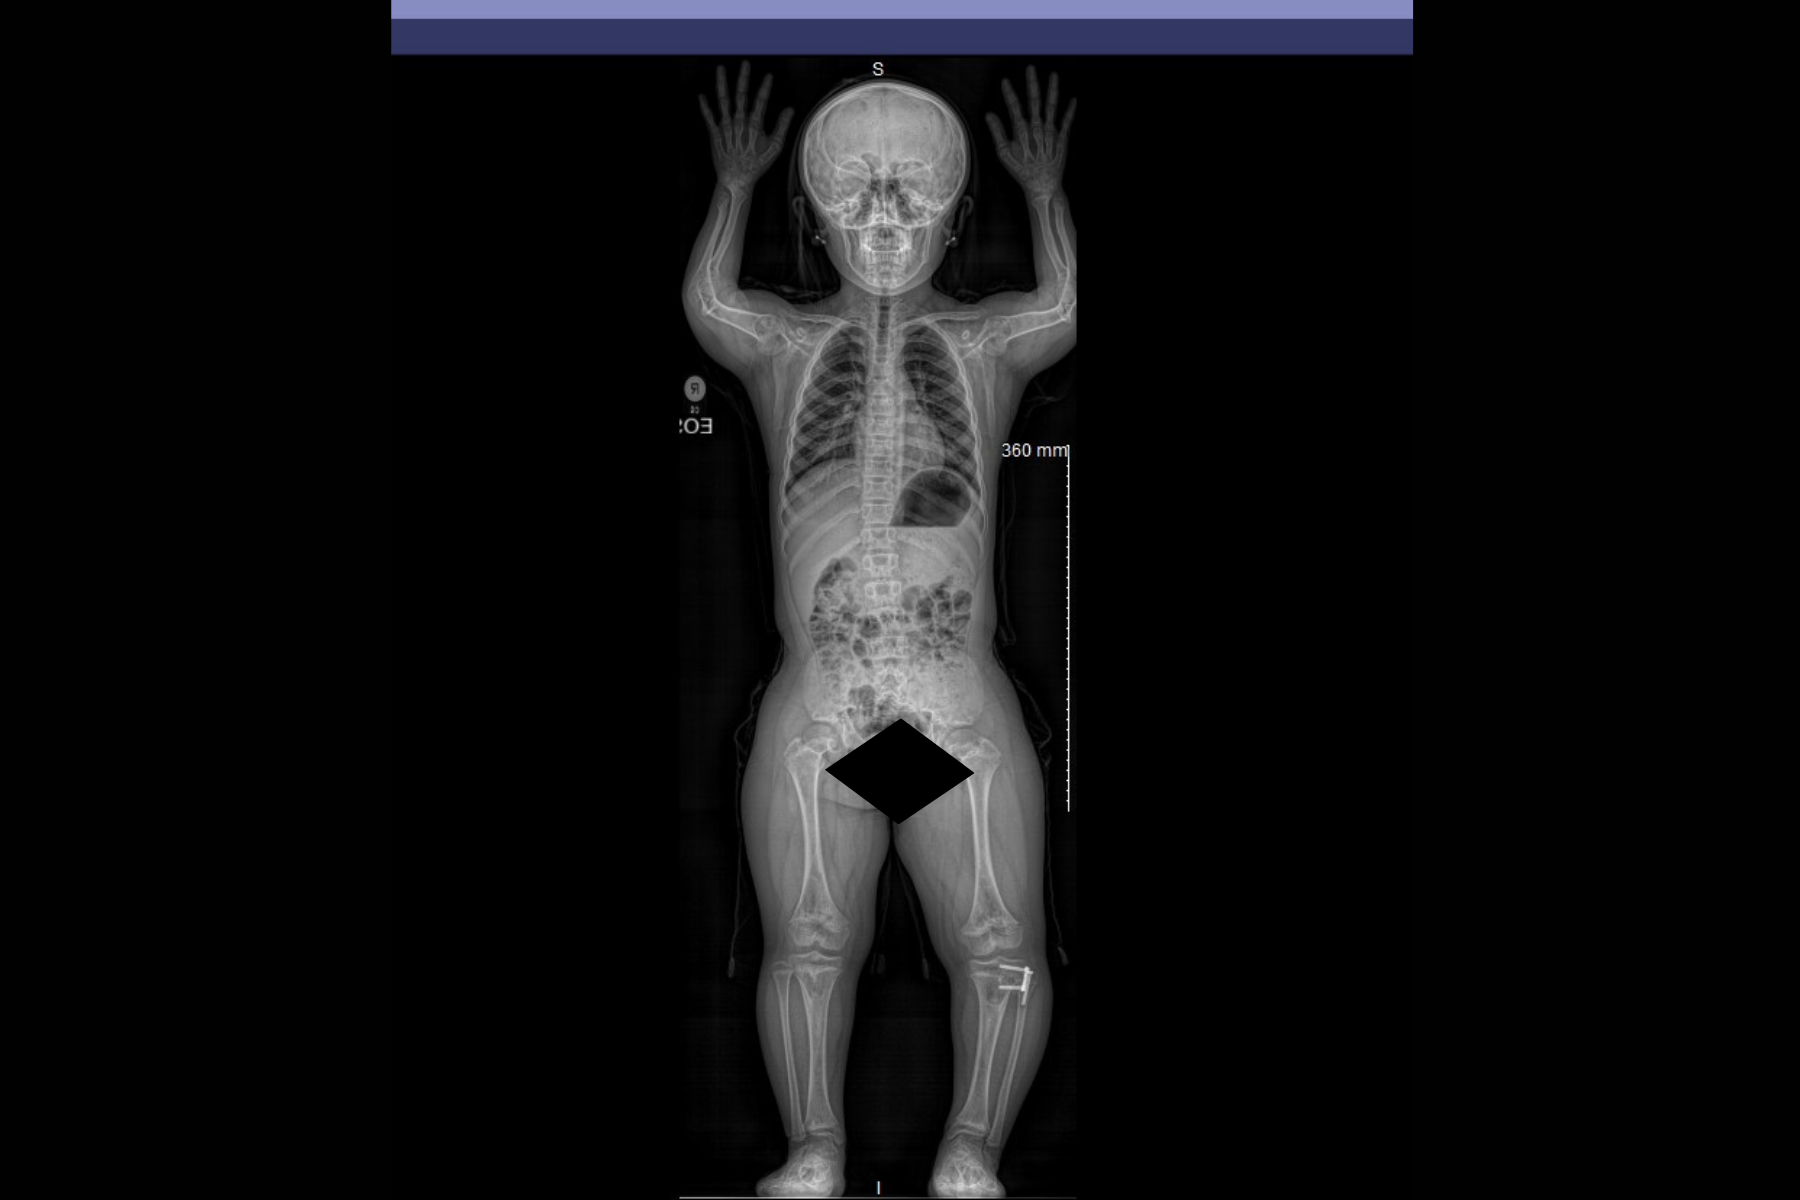

* EOS imaging for low-dose full-body alignment evaluation.